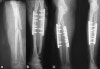

전위가 있는 경우는 수술적 치료로 해부학적 정복 및 견고한 내고정을 시행합니다.

외고정 장치, 골수강내 금속정 고정, 압박 금속판 고정 등을 이용할 수 있습니다.